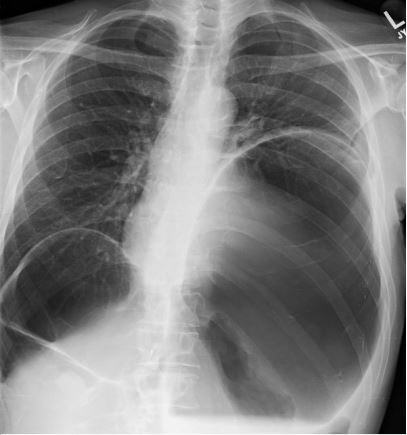

10 days later the patient returned to outpatient cardiology clinic for an echocardiogram and was noted to have a large pericardial effusion along with evidence of impaired relaxation of the left ventricle during diastole (Figure 1). Following transfer to the ED, he was noted to have a heart rate of 113 bpm and blood pressure of 129/70 mmHg; his respiratory rate, oxygen saturation and temperature were within normal limits. A chest x-ray ordered for his mild shortness of breath revealed a massively dilated, air-filled structure in the left upper quadrant with severe compression of the left lung and heart(Figure 2). A CT scan demonstrated massive dilation of a loop of bowel measuring 29 cm x 18 cm x 13 cm centered in the left upper quadrant with possible partial sigmoid volvulus (Figure 3).

Figure 2: Clinical image.